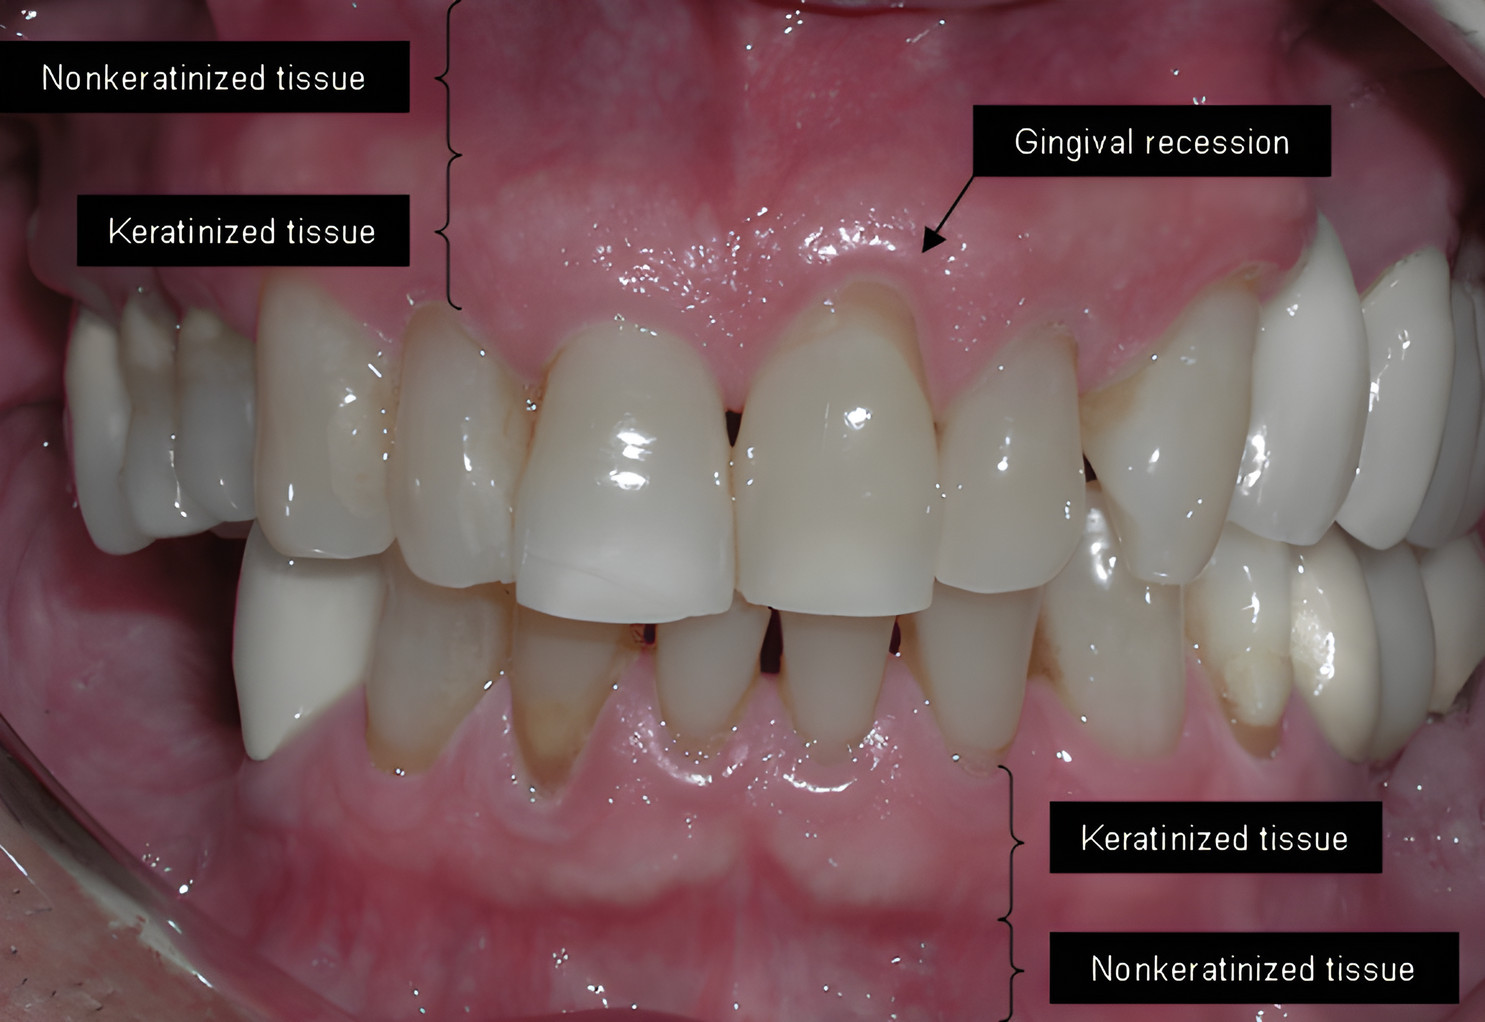

| Gum Inflammation: What really helps with gum Inflammation? | Zahnfleischentzündung: Was hilft wirklich bei Zahnfleisch-Entzündungen? |

| Gum Inflammation Pain – what really helps | Zahnfleischentzündung Schmerzen – was hilft wirklich |

| Gum recession can be quite alarming. Not only is it painful, it can also lead to pockets or gaps between the teeth and gums, allowing harmful bacteria to build up. | Zahnfleischrückgang kann ziemlich alarmierend sein. Es ist nicht nur schmerzhaft, es kann auch zu Taschen oder Lücken zwischen den Zähnen und dem Zahnfleisch führen, so dass sich schädliche Bakterien bilden können. |

| According to WebMD, it can cause severe damage to the supporting tissues and bone structure of the teeth, as well as eventual tooth loss. | Laut WebMD kann es zu schweren Schäden im Stützgewebe und in der Knochenstruktur der Zähne sowie zu eventuellem Zahnverlust führen. |

| So, what causes the gums to recede? | Also, was bewirkt, dass sich das Zahnfleisch zurückbildet? |

| Believe it or not, a study published in the Journal of Periodontology Online found that one of the causes is actually when you don't take enough time for your tooth brushing routine. | Glaube es oder nicht, eine Studie, die im Journal of Periodontology Online veröffentlicht wurde fand heraus, dass eine der Ursachen tatsächlich ist, wenn du dir zu wenig Zeit nimmst für deine Zahnputz-Routine. |

| Another Cause is Genetics | Eine weitere Ursache ist die Genetik |

| According to WebMD, 30% of the population is predisposed to periodontal disease. If you're part of that number, you'll always be at increased risk, no matter how clean you brush. | Laut WebMD sind 30% der Bevölkerung paradontos veranlagt. Wenn du zu dieser Zahl gehörst, wirst du immer ein erhöhtes Risiko haben, egal wie sauber du putzt. |

| Not surprisingly, another cause of gum recession is smoking. According to Simple Steps Dental, smoking is one of the biggest factors contributing to the development of gum problems, including gum recession. | Nicht überraschend ist eine andere Ursache für Zahnfleischrückgang das Rauchen. Laut Simple Steps Dental ist Rauchen einer der grössten Faktoren, die zur Entwicklung von Zahnfleisch-Problemen beitragen, inklusive Zahnfleischrückgang. |

| So, what can you do about receding gums? Do you just have to put up with it? Fortunately not! | Also, was kannst du gegen Zahnfleischrückgang tun? Musst du es einfach so ertragen? Zum Glück nicht! |

| There are several natural remedies that have been found to combat gum recession. | Es gibt verschiedene natürliche Heilmittel, die zur Bekämpfung von Zahnfleischrückgang gefunden wurden. |

| Note that these remedies are naturally most useful when the problem is discovered before it gets to the point where surgery is required. | Beachte, dass diese Mittel natürlich am nützlichsten sind, wenn das Problem entdeckt wird, bevor es zum Punkt kommt, an dem eine Operation erforderlich ist. |